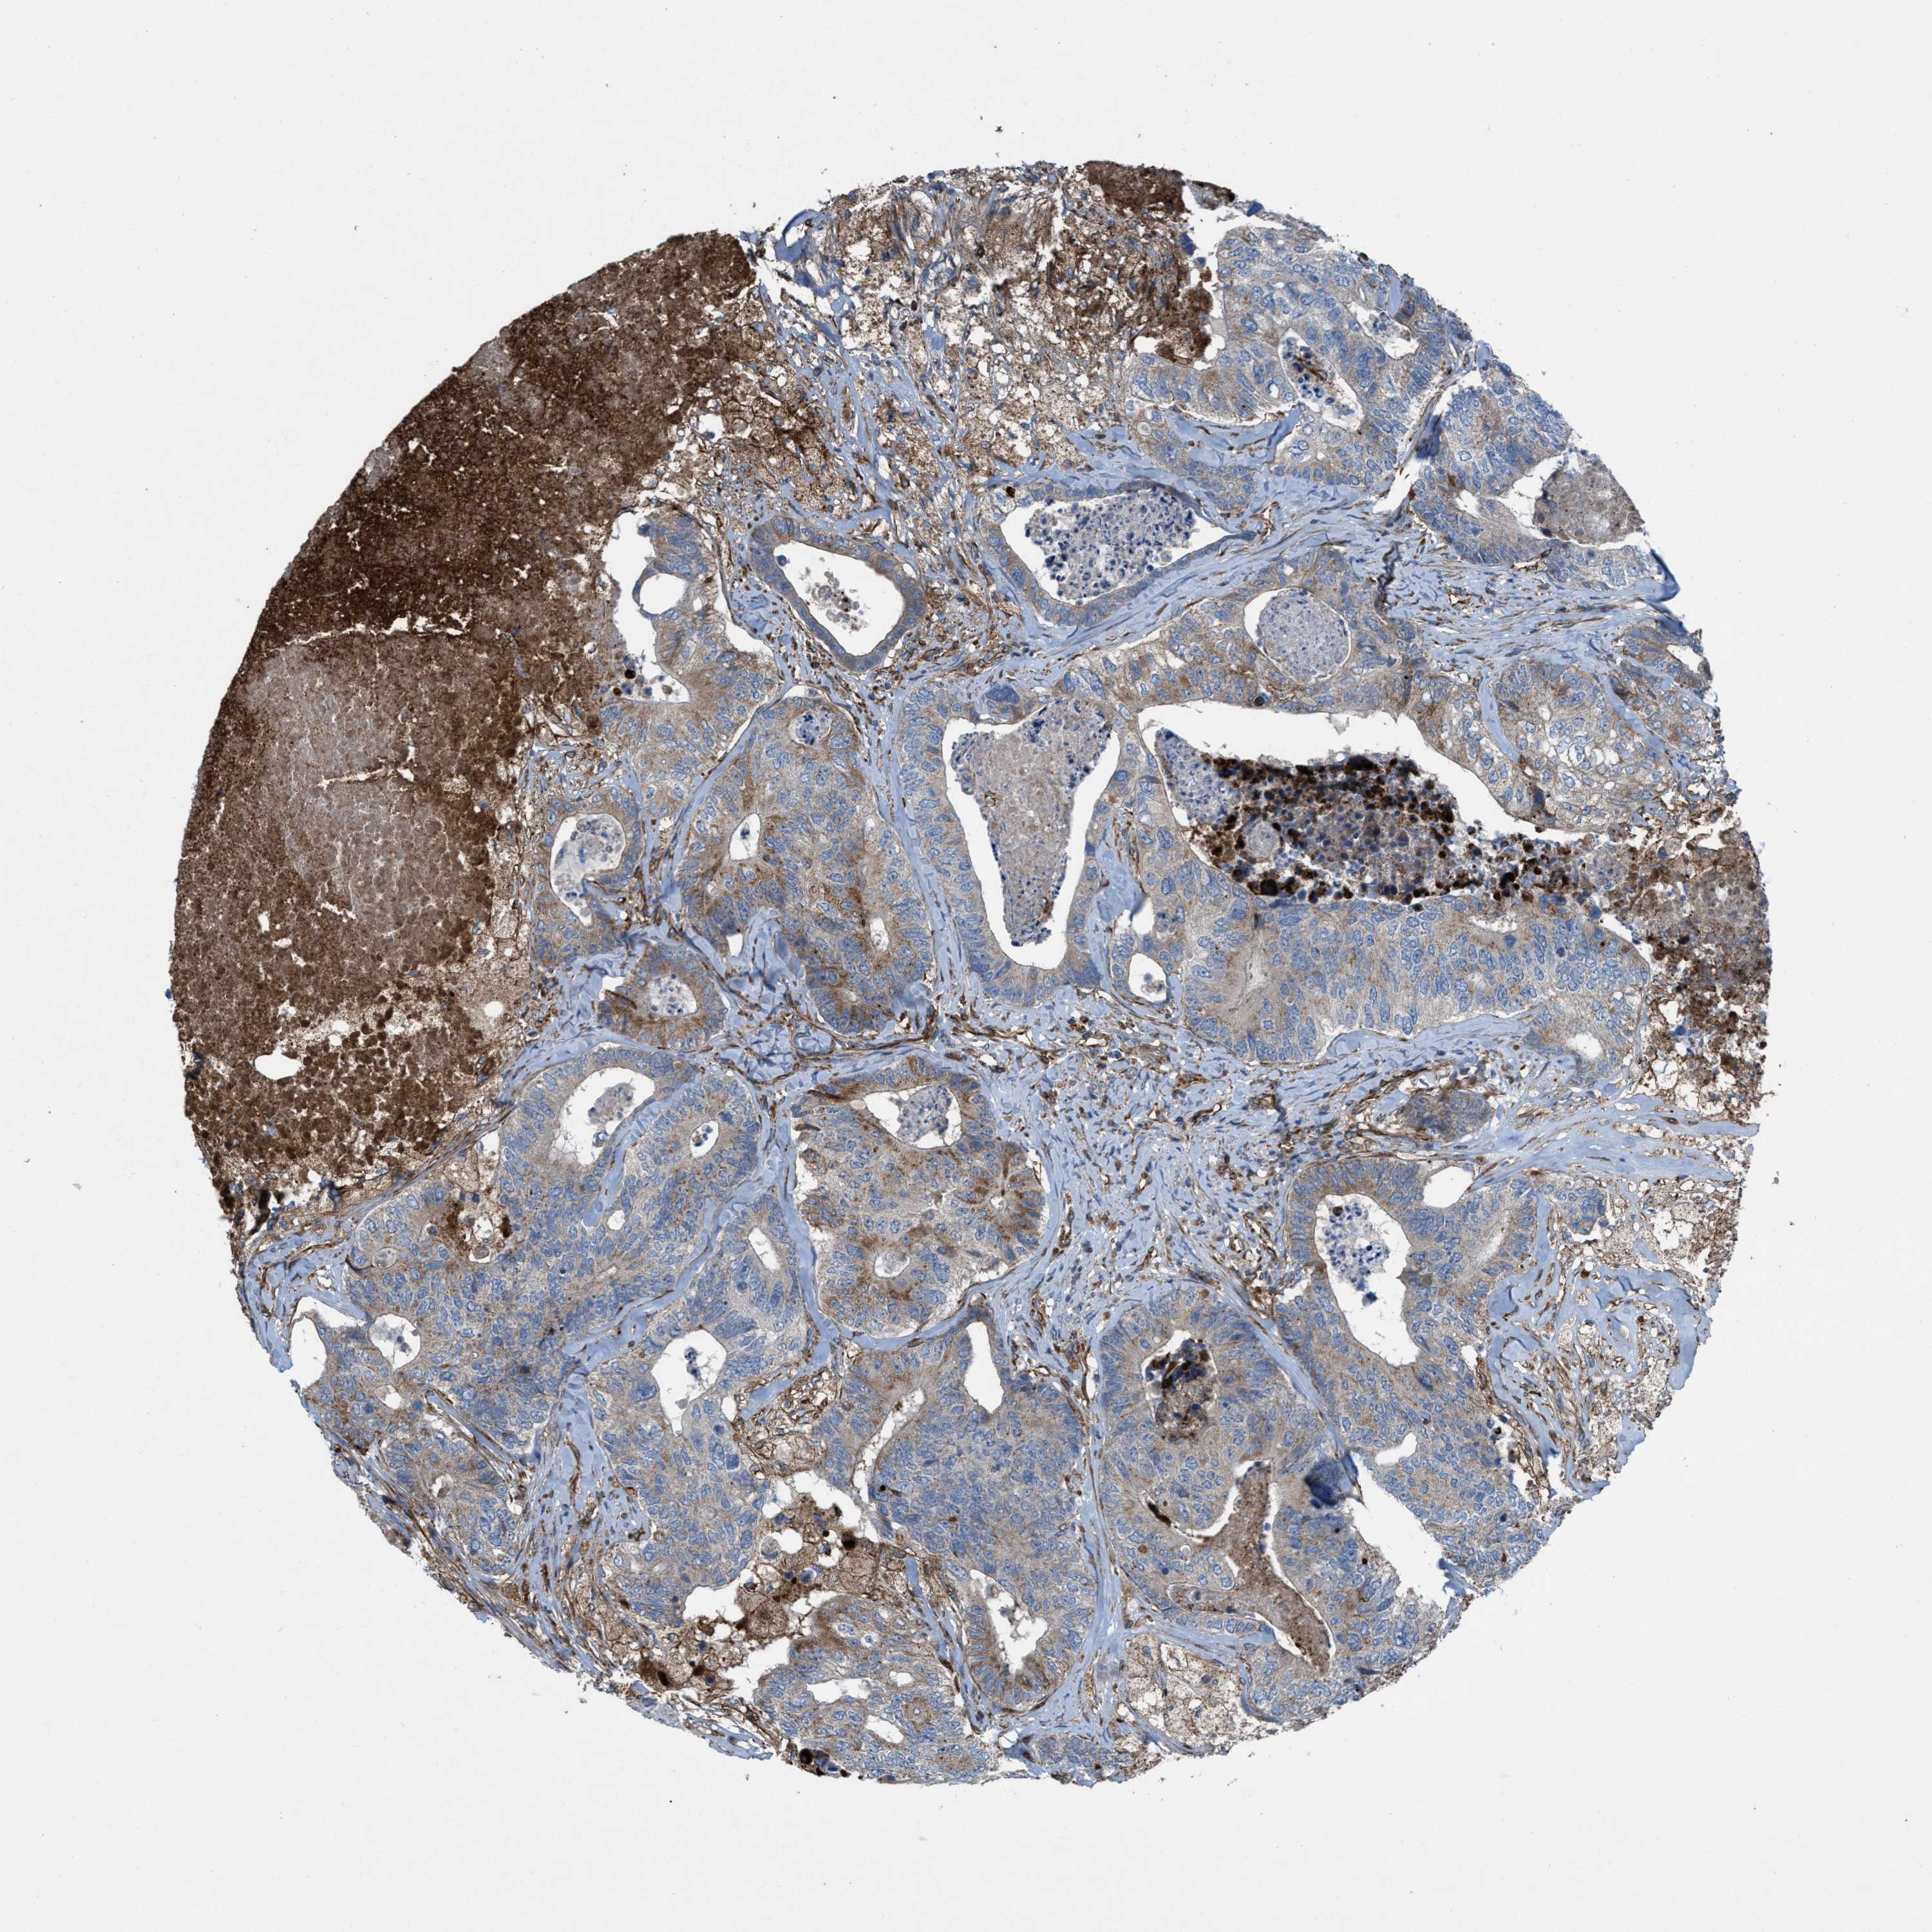

CANCER COLORECTAL CANCER Show tissue menu

Colorectal cancer

Human cancer

Colon adenocarcinoma

Rectum adenocarcinoma